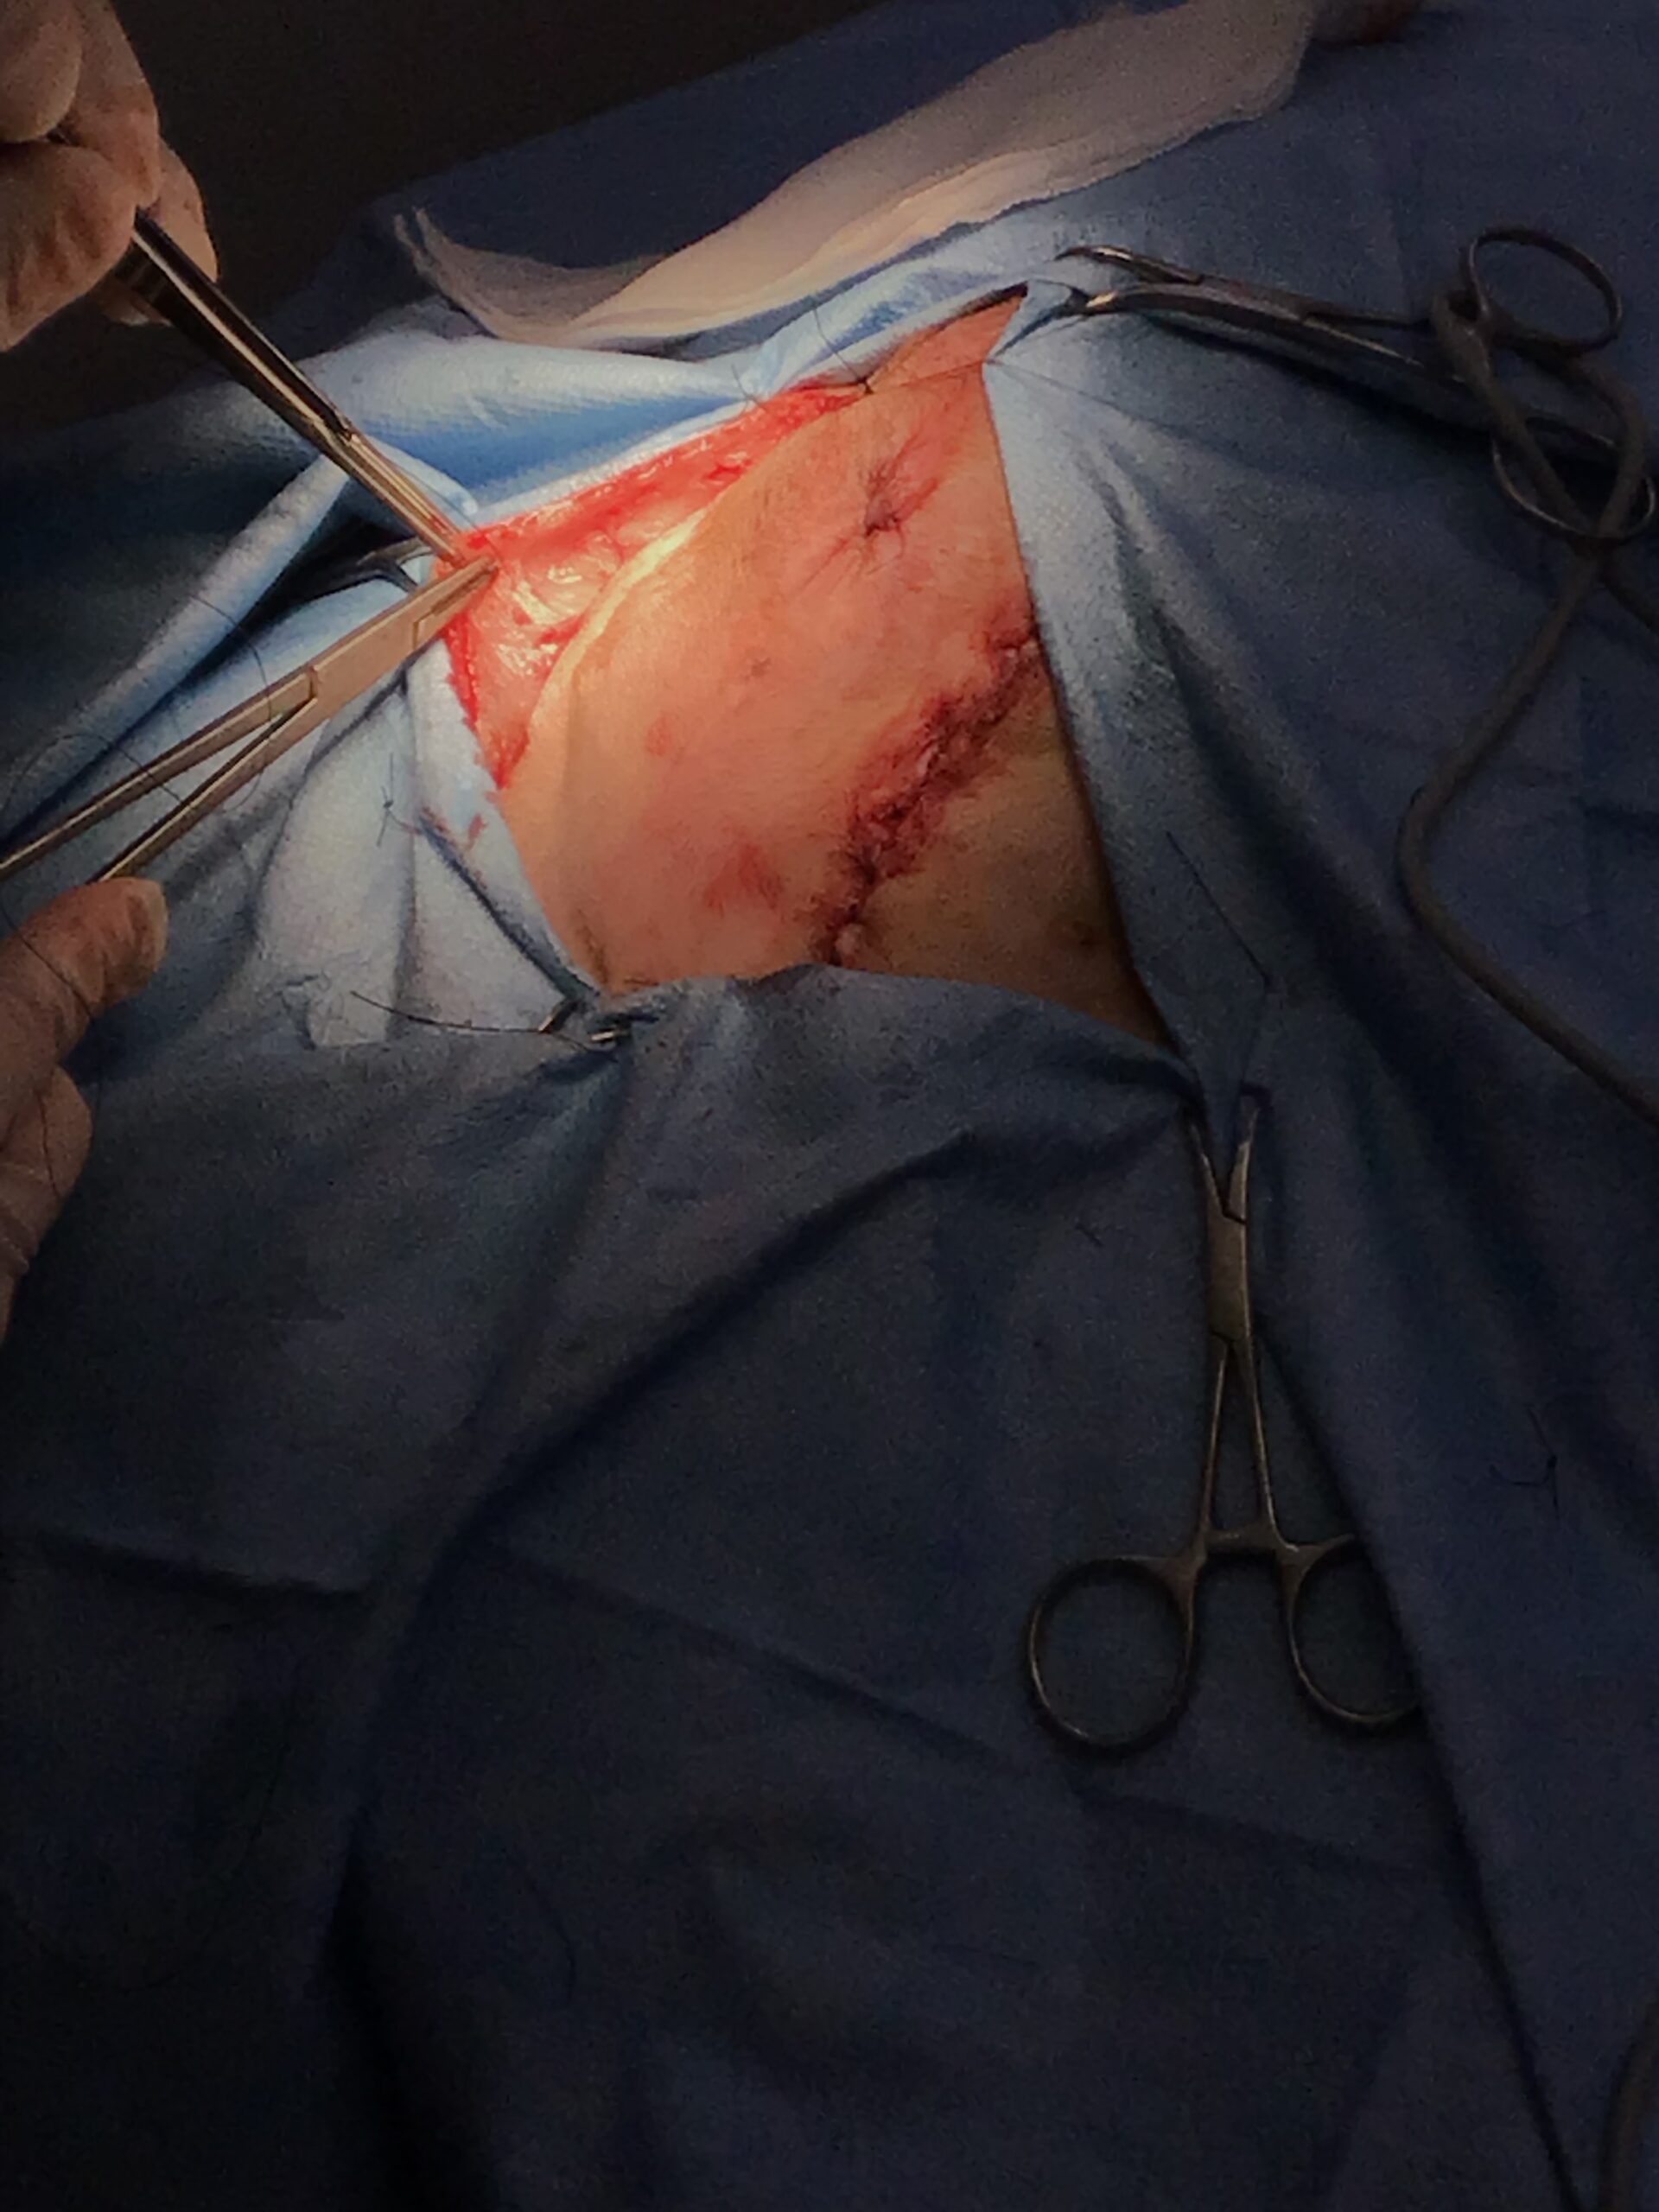

本症例には、時期を分けて2つの大きな外科的介入を行いました。

加えて、会陰ヘルニアの根本的な発症要因となる「前立腺肥大」を退縮させ、将来的な再発リスクを低下させるために、去勢手術も同時に実施しました。

This post details our surgical and medical approach to a complex case involving recurrent severe perineal hernia and a malignant liver lymphoma in a senior dog. We emphasize the grim reality of untreated conditions and the severe risks of anesthesia when underlying heart and respiratory diseases are present. To maximize safety, we exclusively use local infiltration anesthesia. Due to a lack of available autologous tissue, a polypropylene mesh and extensive organ pexy (both colon and bladder fixation to the abdominal wall) were required to prevent fatal urethral obstruction and re-herniation. Additionally, simultaneous castration was performed to shrink the enlarged prostate, a key factor in hernia development, thereby reducing the risk of recurrence. For the liver tumor, given its deep location at the liver base and the high risk of fatal bleeding, we opted for a biopsy which confirmed lymphoma. Unfortunately, the patient’s elevated bilirubin and the family’s preference for a compromised, single-agent chemotherapy protocol led to early drug resistance. We candidly discuss the harsh realities of end-stage cancer—it is a painful decline characterized by severe cachexia and organ failure that palliative care can only partially ease. Furthermore, we outline our strict early discharge policy (1-3 days), the physical limitations of our unstaffed overnight remote monitoring, and our referral policy for highly specialized surgeries. We believe in providing honest, logical medical facts rather than false hope, ensuring families can make fully informed and responsible decisions.